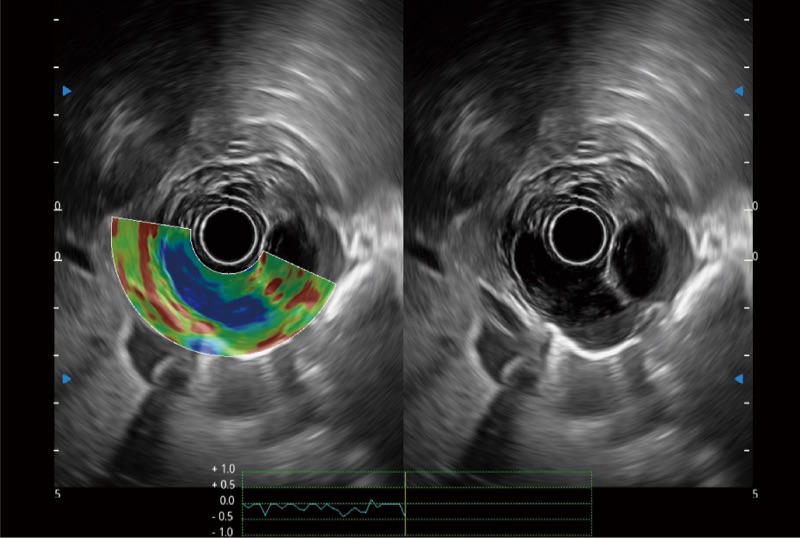

位移矫正技术

不可靠区域自动剔除

弹性定量分析软件